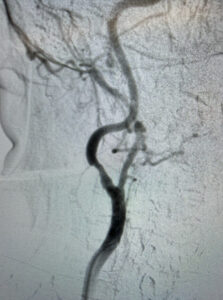

Ένδαγγειακή αντιμετώπιση καρωτιδικής νόσου